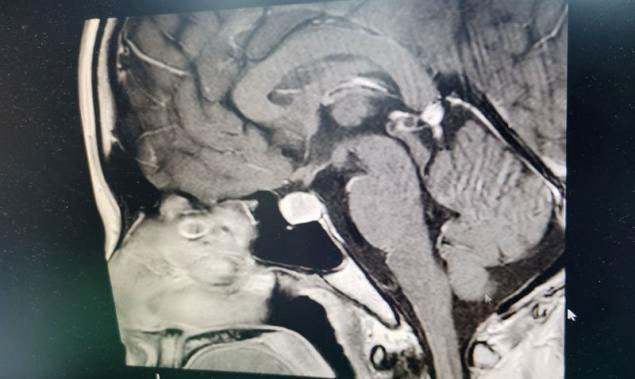

▲ 垂体占位

入院检查鞍区MRI平扫+增强显示:垂体前叶右侧份见一类椭圆形异常信号,直径约1.0×1.0×1.1cm。右侧鞍膈抬高、右侧鞍底轻度下陷,垂体柄向左偏移。右侧海绵窦受推移。检查泌乳素1796.44μIU/mL,远超正常值。

结合病史、影像等,神经外科6B病区潘仁龙主任、李士其教授、吴治群博士会诊后,考虑为泌乳素型垂体瘤,并且患者已经出现垂体腺瘤卒中,手术指征明确,应尽快手术治疗。